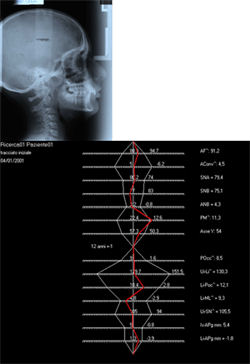

La radiografía panorámica evidencia la presencia de todos los elementos dentarios, inclusive los gérmenes dentarios de los terceros molares. El análisis cefalométrico revela una discrepancia esquelética sagital, con un ANB de 5, un perfil óseo ligeramente convexo y un patrón de crecimiento braquifacial. Por otra parte se realizó una clasificación de crecimiento del paciente, determinando que el mismo pertenece a una categoría auxológica 5 y tipo rotacional identificado como A1NN (segun Petrovic)(9,10), en donde A representa la rotación anterior de la mandibula, 1 indica la proporción de crecimiento entre el maxilar superior y la mandibula constante, N indica una relación sagital normal entre los maxilares y N indica una relación vertical normal entre los maxilares (Normal-bite). Las bases de los maxilares (superior e inferior) tienen una longitud media. Los incisivos superiores e inferiores muestran una inclinación adecuada respecto a las bases óseas. (Fig. 5, a-b)

Fig 5 (a-b): Análisis cefalométrico inicial según Illinois